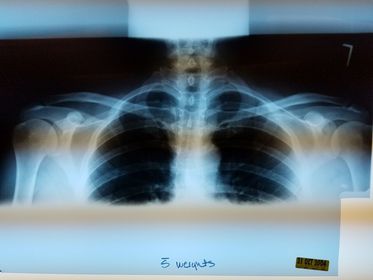

Bilateral AC Joints w/ weights